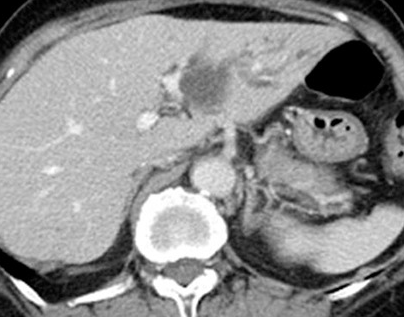

Abdominal CT scan. Hemorrhagic rupture of a simple hepatic cyst without active hemorrhage. The presence of free intraperitoneal fluid is noted (Courtesy Dr. V. Penopoulos)